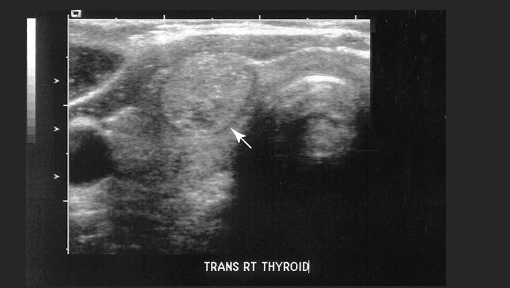

A patient presents with a small mass palpated in a recent physical exam and normal lab values. A mass is identified in the inferior portion of the right thyroid lobe. On the basis of this clinical history, the sonographic findings are most suspicious for a

B. Adenoma